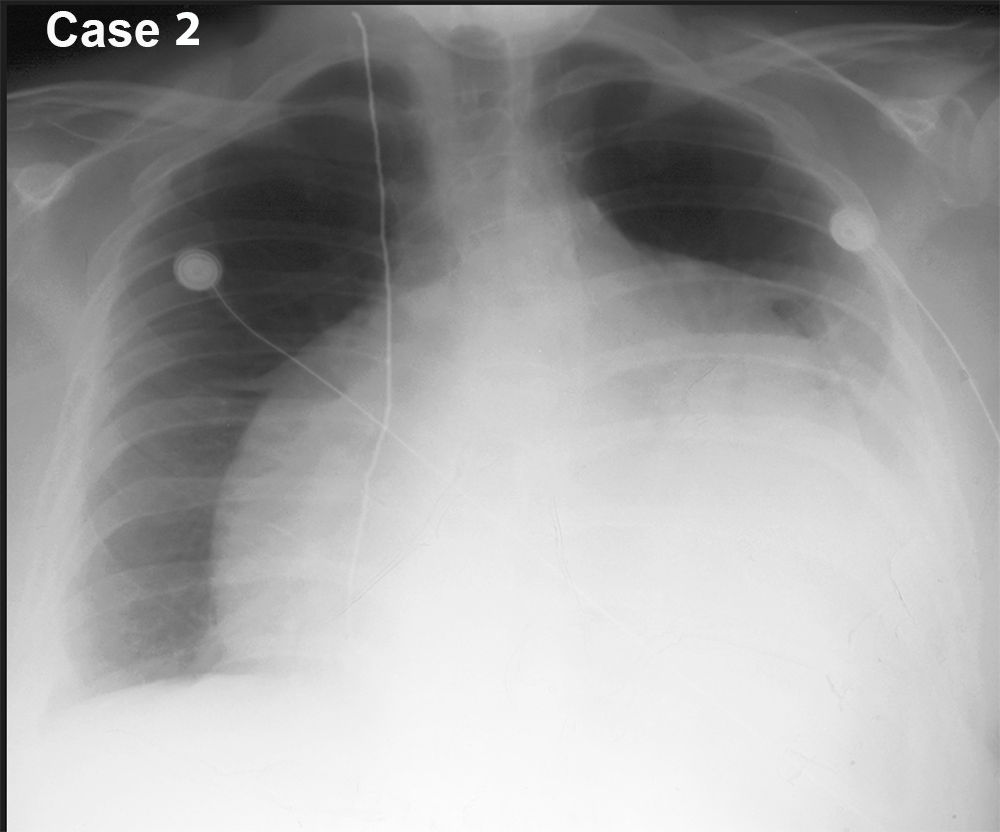

You are given a review of the ABCDE approach to frontal CXR interpretation and five cases to preview before class.

For each of these five cases, try to identify what is most abnormal, using the ABCDE framework to organize your search. Be descriptive! Try not to jump to conclusions regarding the final diagnosis. We will discuss each case in more detail in class. You can also consider what the next imaging study should be, and can make use of the ACR Appropriateness Criteria to help in this decision. You can also search the STR website for educational materials pertinent to each case.